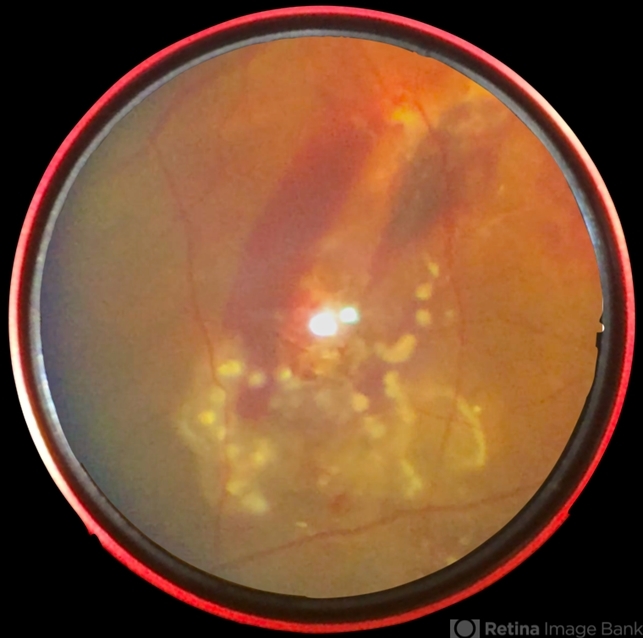

- worm, laser photocoagulation, subretinal hemorrhage, uveitis, smartphone fundus photography

- 42-year-old, male came with chief complaints of diminished vision and floaters in right eye for past one week. On fundus examination noted to have subretinal haemorrhage and edema at the posterior pole and a subretinal live mobile worm at the periphery. Laser photocoagulation done followed by pars plana vitrectomy.